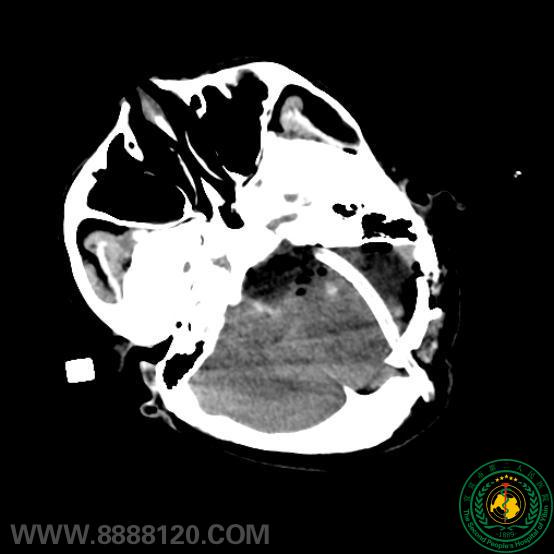

苦战7小时,宜宾市第二人民医院神外一科顺利成功切除后颅窝巨大肿瘤

苦战7小时,宜宾市第二人民医院神外一科顺利成功切除后颅窝巨大肿瘤40193